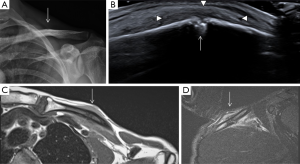

Clavicle fractures mostly occur in young adults as the result of a sports injury or direct trauma (Figure 10). Clavicle fractures secondary to minor trauma have been rarely reported associated to a tumour, such as multiple myeloma (25). In cases of fractures secondary to minor trauma, a pathological aetiology should always be excluded. Most nondisplaced or minimally displaced injuries can be treated conservatively (26).

Sternoclavicular dislocations account for fewer than 5% of all dislocations of the scapular belt. Most cases of anterior dislocation of the sternoclavicular joint do not present with any clinical symptoms. However, some patients may develop chronic anterior instability and may continue to present symptoms. In these cases, surgical treatment is indicated (27). Sternoclavicular dislocations usually occur following traumatic events. Anterior dislocation often follows motor vehicle accidents, or occurs during sporting activities. Posterior dislocation is considered less common and it is classically secondary to indirect trauma. When a force is applied to the posterolateral shoulder, the lateral portion of the clavicle is displaced anteriorly. With a taut costoclavicular ligament acting as a fulcrum, the medial clavicle is then levered behind the sternum. Direct trauma to the anteromedial portion of the clavicle is a considerably less frequent condition (28).

Nevertheless, other authors contradict previously reported results; in a study of 41 patients with sternoclavicular joint pain related to trauma, MRI found 24 subluxations (59%), which antero-posterior axis was displaced anterior in three patients (7%) and posterior in 11 patients (27%), whereas supero-inferior axis was superior in 17 patients (41%) and inferior in two (5%). The authors explained this discrepancy based on their patient population, consisted of patients with more delayed and chronic symptoms (29). Dislocation of the sternoclavicular joint should always be considered in a trauma patient with pain, swelling, or deformity over the medial clavicle. Because of the potential for serious complications with a posterior dislocation, rapid diagnosis is essential. In practice, this will usually involve a chest radiograph, one of the specialized sternoclavicular views, followed by an immediate CT examination if possible (27). In fact, posterior sternoclavicular dislocations may be subtle or not visualized on conventional radiography. Therefore, when there is a clinical suspicion for this entity, CT with intravenous contrast material administration can be used to confirm the diagnosis and evaluate for possible associated vascular injury (1).